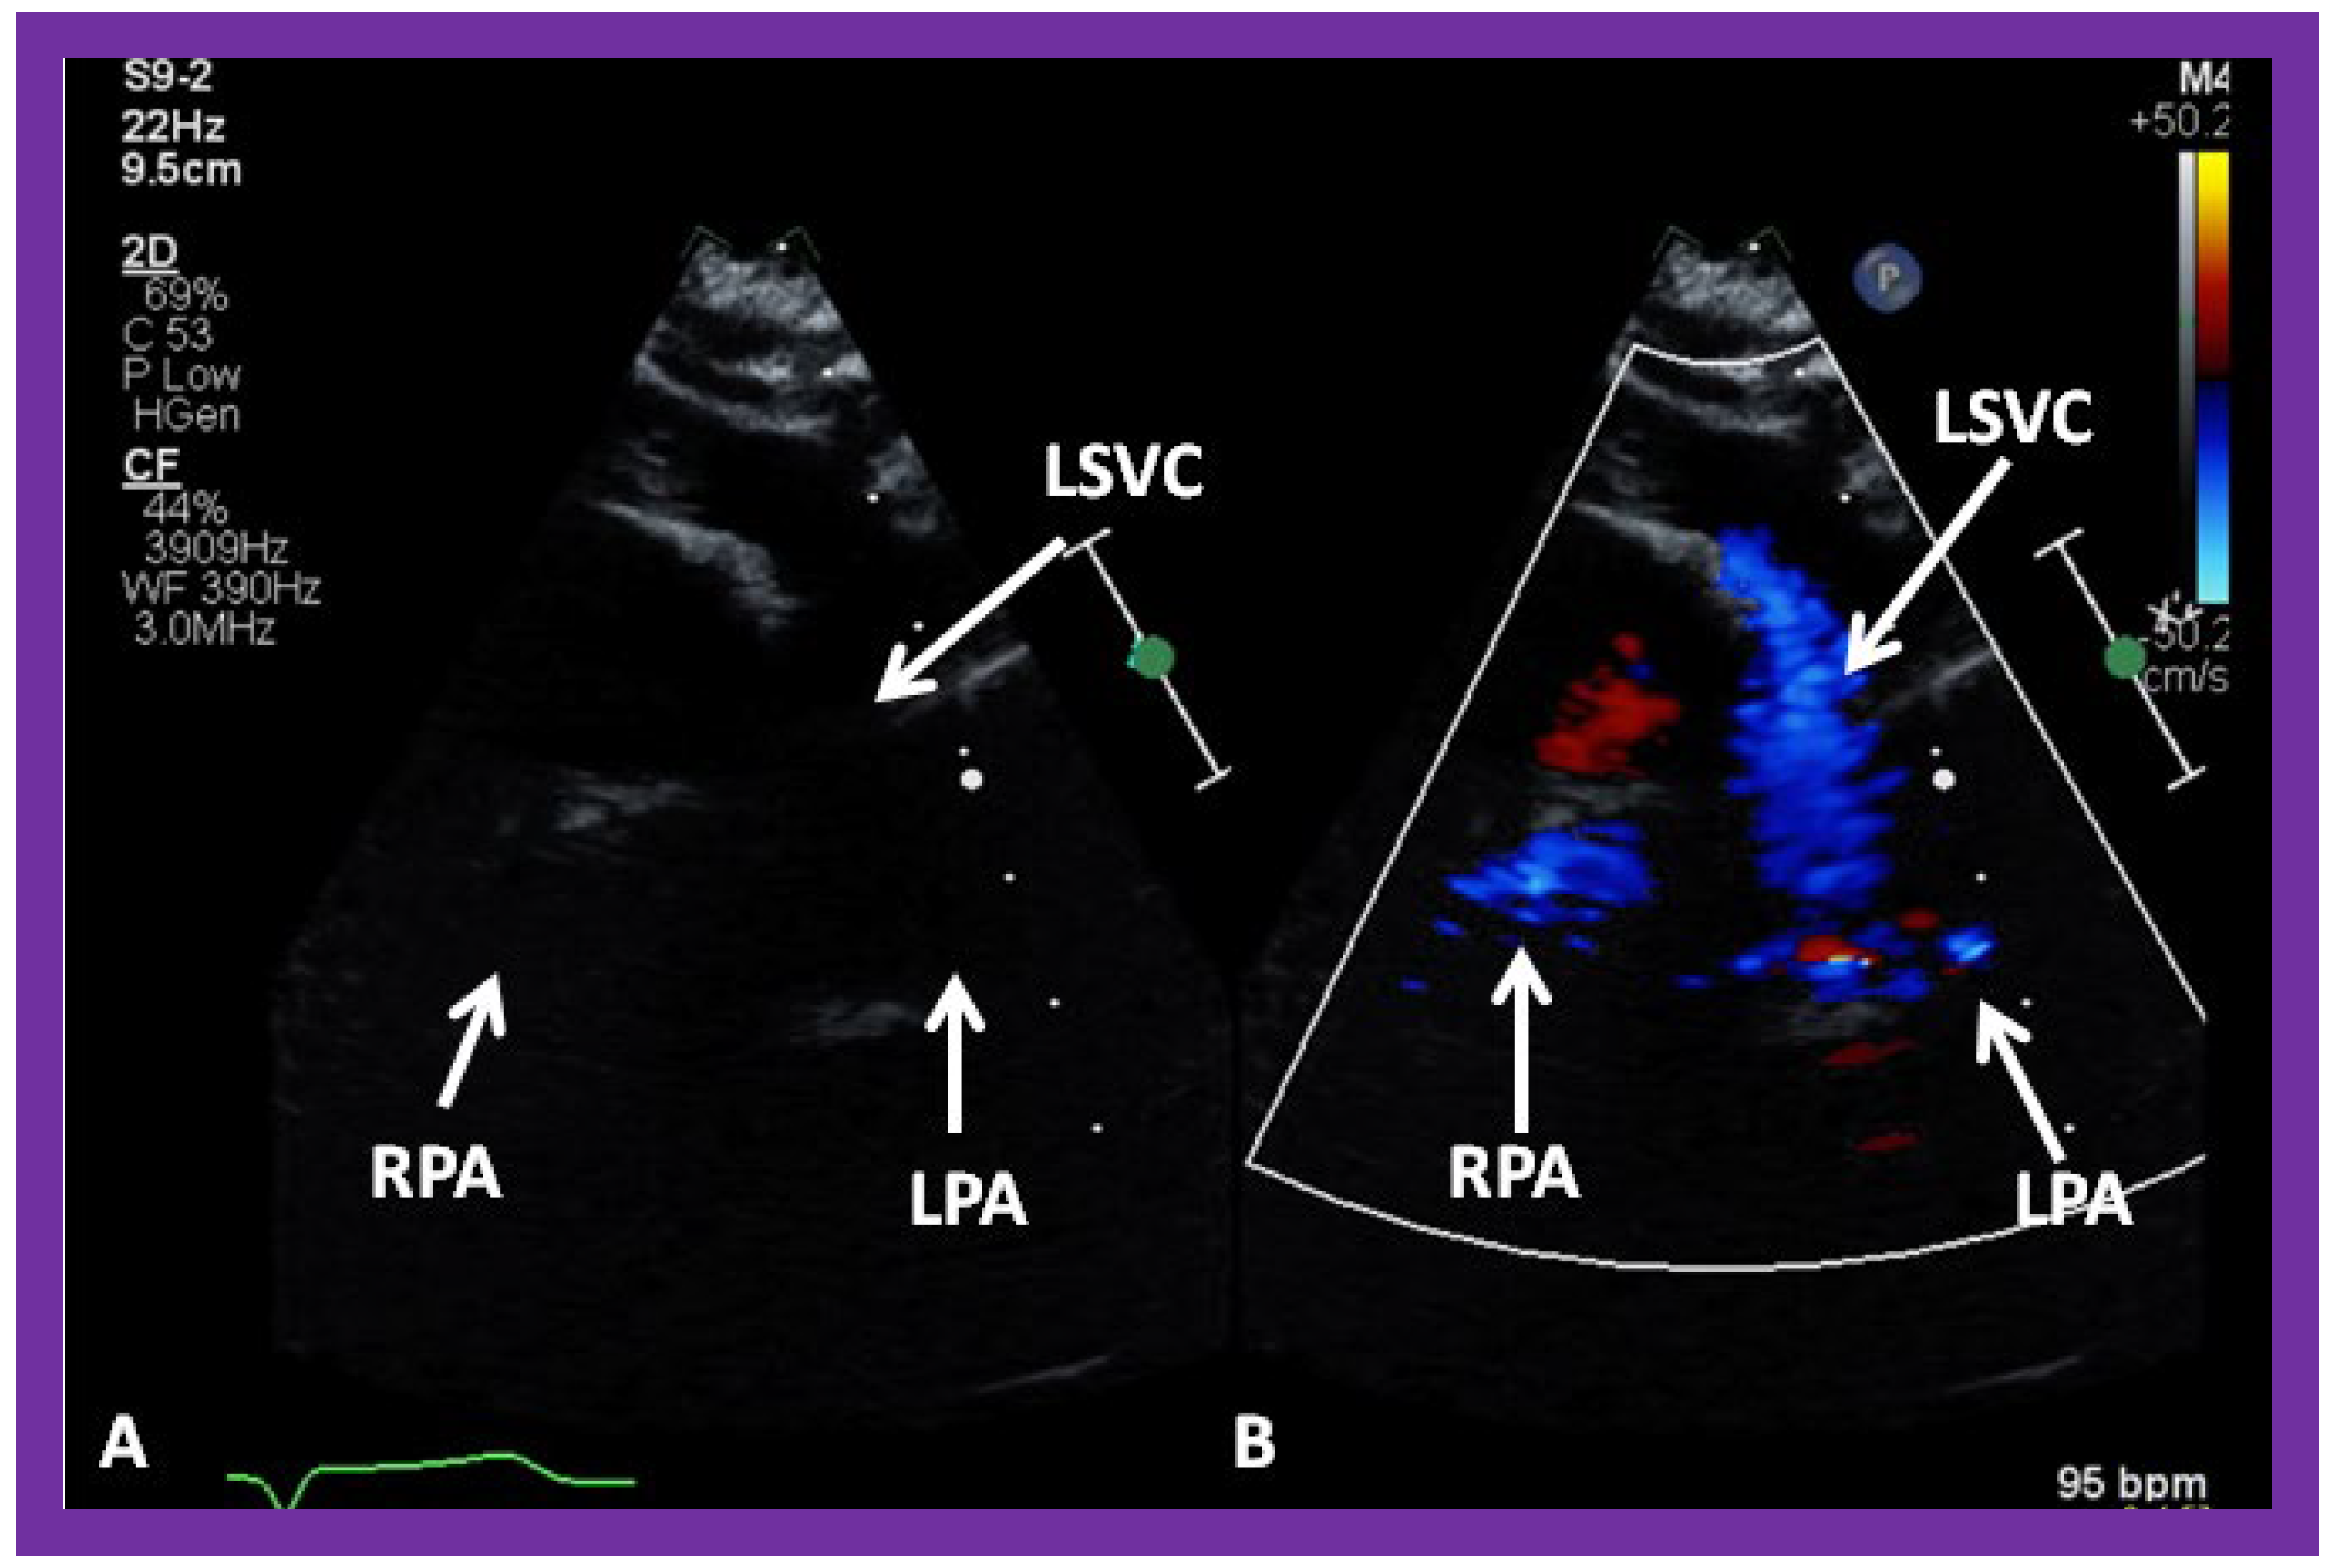

Figure 30. (A,B) Selected video frames from suprasternal notch view demonstrating left sided bidirectional Glenn shunt. In (A), the right (RPA) and left (LPA) pulmonary arteries are faintly seen by 2D. On color Doppler study, the visualization is slightly better (B). LSVC, left superior vena cava.

In patients who have a persistent left SVC entering the heart via the coronary sinus, bilateral bidirectional Glenn procedures are performed, especially if the inter-connecting left innominate vein is small or absent. An example of left sided bidirectional Glenn is shown in Figure 30. In subjects who have infrahepatic interruption of the inferior vena cava (IVC) with azygos or hemiazygos continuation (into the right or left SVC, respectively), a Kawashima procedure is performed. In these patients, echocardiographic imaging of the Glenn/Kawashima is similar to that of regular bidirectional Glenn (Figure 25, Figure 26 and Figure 27).